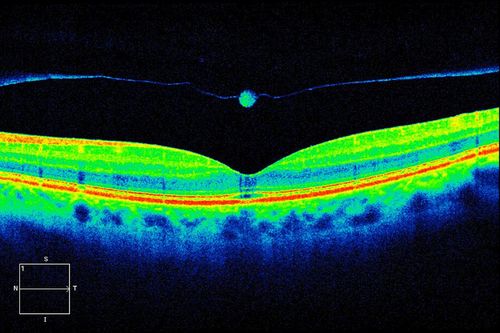

HD OCT Image of Operculum

MACULAR HOLE

Mayo Clinic Jacksonville, Florida

Cirrus- HD OCT